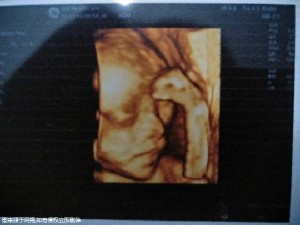

什么樣的人不適合做試管嬰兒

不適合做試管嬰兒的人群主要有以下幾種:1.男性女性雙方任何一方存在嚴(yán)重的精神疾病、泌尿生殖系統(tǒng)急性感染或性傳播疾病等;2.男性女性雙方任何一方接觸了致畸量的射線、毒物、藥物等有害刺激,且處于作用期;3.男性女性雙方任何一方存在酗酒、危險(xiǎn)行為等不良嗜好;4.女方子宮存在異常發(fā)育不全、子宮畸形等不具備妊娠功能的情況,以及有不宜妊娠或妊娠后導(dǎo)致疾病加重的全身性疾病,如嚴(yán)重的心臟病、腎衰、肝衰等。